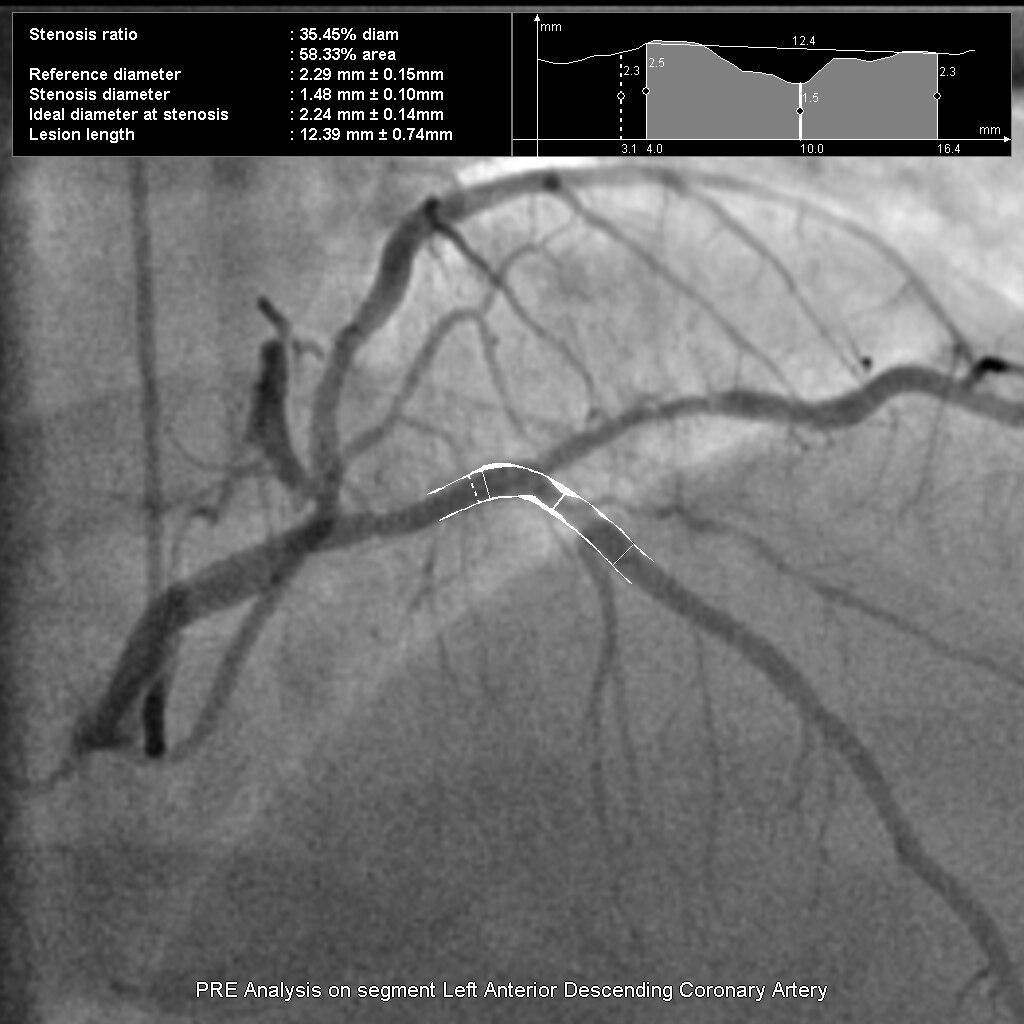

Великолепное качество изображения при низкой дозе

Цифровой квадратный плоскопанельный детектор Revolution имеет уникальную конструкцию, представленную фотодиодной матрицей с аморфным кремнием на монолитной основе без характерных швов. Толщина сцинтиллятора и электронный шум оптимизированы таким образом, чтобы максимально увеличить эффективность использования дозы облучения.

Детектор обладает одним из самых высоких в отрасли коэффициентом квантовой эффективности (DQE). Высокий DQE позволяет получать изображения более высокого качества при применении тех же параметров дозы или изображения прежнего качества при сниженной дозе облучения. Функция Smart Fluoro оптимизирует качество изображения на всех уровнях дозы облучения, обеспечивая возможность использования минимальной дозы облучения при оптимальном качестве изображения.